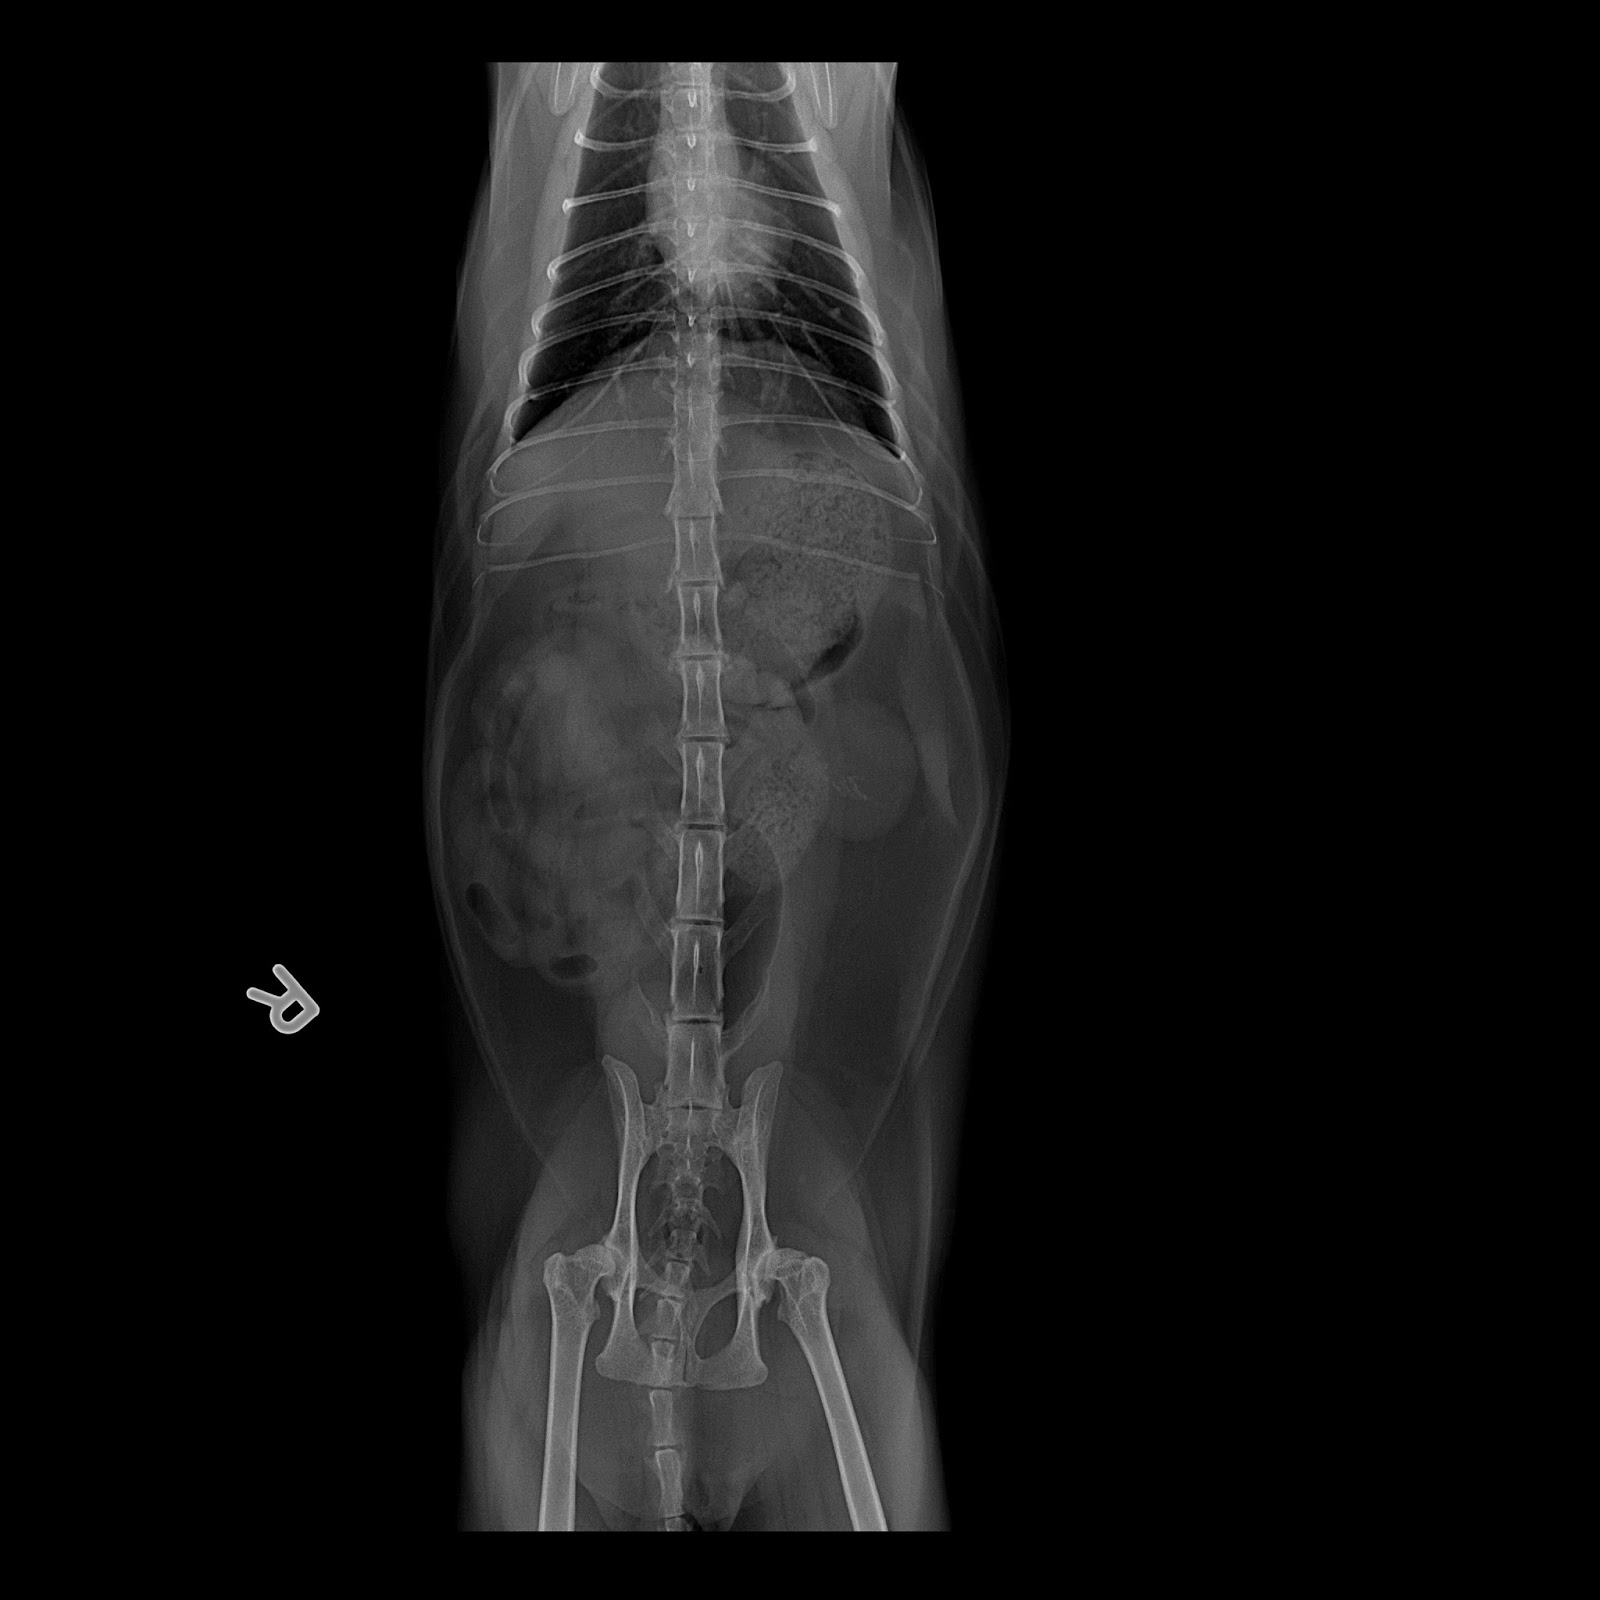

From www.clubpets.com.sg

How to Tell if Your Cat Has Kidney Problems How Can You Tell If A Cat Has Kidney Stones Small kidney stones often don't present symptoms and are only detected during a. Signs of kidney stones in cats. The signs and symptoms of kidney stones could include: Understanding how kidney stones can affect a cat's health is important. Symptoms of kidney stones in cats. Signs of kidney stones in cats include frequent urination, blood in the urine, and straining. How Can You Tell If A Cat Has Kidney Stones.